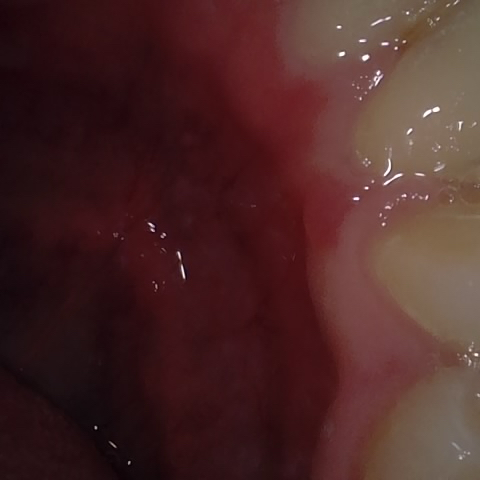

NHD20738

Annotated as "Bad"